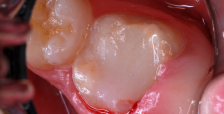

A 9-year-old boy had a partially erupted mandibular first molar with much hypocalcification of the occlusal surface and a large caries lesion involving the occlusal and buccal surfaces (Figure 1). The patient complained of continuing sensitivity to cold stimulus and air inspiration. Because the tooth was only partially erupted, consideration for stainless steel crown full coverage had to be delayed. As an interim repair, it was decided to debride the carious tooth substance and place a light-hardened calcium silicate/mineral trioxide aggregate (MTA) liner, followed by a bonded restoration. After inferior alveolar block anesthetic injection and cotton roll isolation, cavity outline form was cut using a high-speed, water-cooled, medium-grit cylindrical diamond bur (Figure 2). Insufficient eruption precluded use of a rubber dam. A large, round bur at slow speed was used to debride the carious enamel and dentin. The prepared surfaces were swabbed for two 60-second applications of a 5% glutaraldehyde/HEMA solution for desensitization and disinfection of the preparation.6,7 Cavity liner was then injected and spread over the deepest sections of the cavity floor and hardened with the visible light beam (Figure 3). After a self-etching bonding agent was applied over the remaining enamel surfaces, without the need for any type of matrix, an RMGI bioactive ionic resin-based composite was injected, in one portion, into the preparation and spread over the four cusps using a ball burnisher. This restorative complex was then photo-polymerized using two 20-second exposures of the visible light beam (1,200 mW/cm2). The restoration was trimmed and finished with large, round diamond burs at slow speed, and occlusion was evaluated with articulating paper and adjusted.

The tooth was prepared for interim sedative restoration.

Figure 2

Cavity liner was placed and light-hardened.

Figure 3